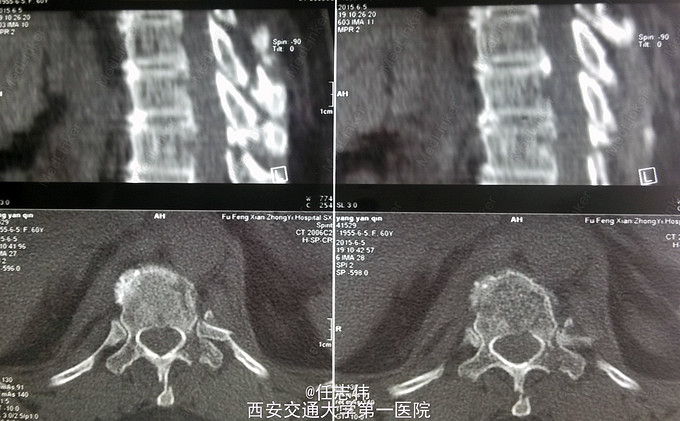

患者女性,60岁,车祸伤致双下肢感觉活动不能8h入院。 8小时前坐农用车时,被横杆撞倒腰部,摔下后感觉胸背部疼痛,双下肢活动不能,伴有短暂昏迷病史。遂来我院就诊。

左侧胸壁广泛压痛,呼吸急促。专科查体:胸背部广泛压痛,自腹股沟平面以下感觉、运动消失,腹壁反射消失,肛门反射消失,巴氏征阴性。双上肢感觉运动正常,骨盆分离挤压试验阴性。

诊断:1.胸11椎体骨折伴截瘫(Frankel A级)2.闭合性胸部损伤,肺挫伤,多发肋骨骨折,双侧胸腔积液 处理:1.急诊入院告病危,心电血氧监护;2.予以甲强龙冲击治疗;3.次日复查胸部CT,查看肺部损伤情况及胸腔积液,后予以右侧放置闭式引流。患者氧合不稳定,2日后复查胸片胸腔积液减少,予以行后路减压内固定融合术。 手术:术中见局部软组织损伤严重,胸11-12棘上、棘间韧带断裂,胸10、11、12双侧关节突有骨折移位,胸11椎板骨折,胸11左侧不能置入椎弓根螺钉,遂行单纯固定。脊髓局部挫伤明显,并有硬膜破损,予以处理。